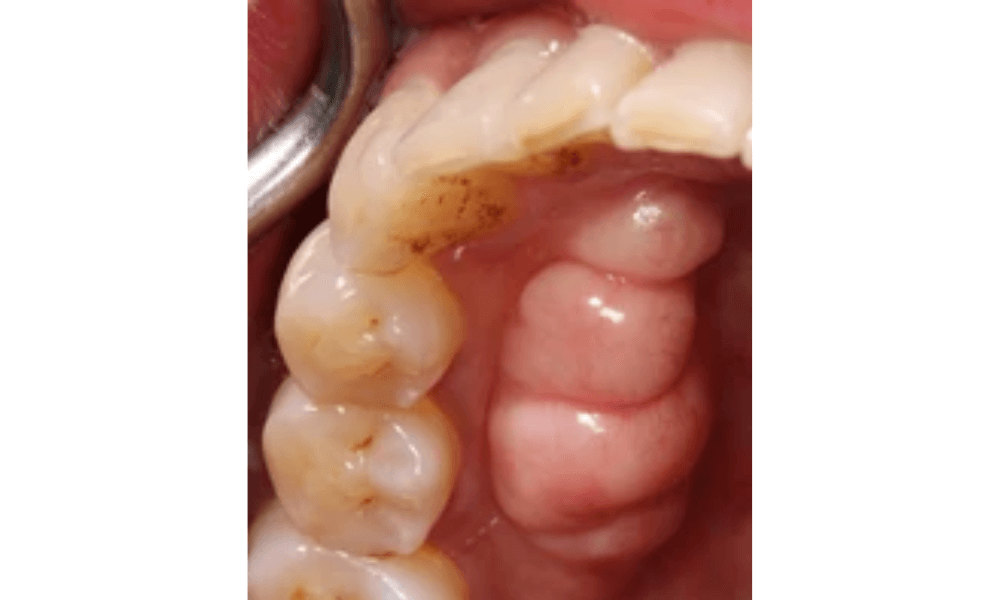

Mandibular Tori Pictures

Mandibular tori are bony growths that appear on the inner surface of the lower jaw. These growths are typically harmless and vary in size and shape. In the pictures provided below, you can observe the different presentations of mandibular tori. These images will help you recognize what mandibular tori look like and understand their typical appearance. If you notice similar growths in your mouth, it’s advisable to consult a dentist for a professional evaluation.